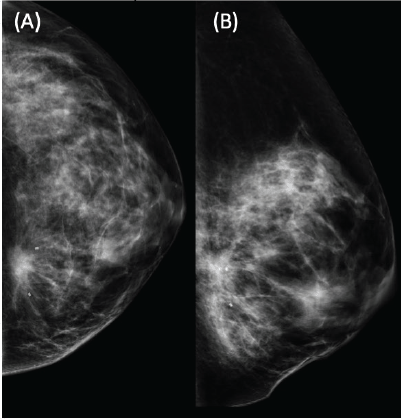

We present the case of a 36-year-old woman, with insulin resistance, without a family history of breast cancer, who consulted for a 6-month evolution self-detected left breast nodule associated with skin retraction. At the physical exam, there was a 20-mm palpable mass retracting the skin at the lower-inner quadrant (LIQ) of the left breast, without clinically evident axillary adenopathies. The patient was studied with mammography [Figure 1] and breast ultrasound [Figure 2], which showed a spiculated mass of 29 × 24 × 14 mm at the LIQ of left breast, with the increased flow at doppler, diagnosed as BIRADS-5. A core biopsy was performed, demonstrating a poorly differentiated invasive ductal carcinoma with positive oestrogen receptor (99%; / ), positive progesterone receptor (90%; ), positive human epidermal growth factor receptor type 2 (HER2) 3 , fluorescence in situ hybridisation for HER2 and Ki-67 30%. The staging study demonstrated an osteolytic lesion compatible with sternal metastasis evident in computed tomography (CT), positron emission tomography (PET)/CT and magnetic resonance imaging (MRI) [Figure 3]. The staging was completed with sentinel lymph node biopsy, obtaining six lymph nodes without metastasis. The primary lesion was marked with two metallic clips guided by ultrasound. The patient completed neoadjuvant ST with Doxorubicin, Cyclophosphamide, Paclitaxel, and HER2-directed therapy with Trastuzumab and Pertuzumab, with a complete clinical response at physical exam and images [Figure 4]. Later, she underwent left partial mastectomy, using percutaneous hookwire for the location of the metallic marker clips. The definitive biopsy demonstrated an area of 27 × 25 × 15 mm of scarring substitutive fibrosis associated with isolated microfocus (less than 1 mm) of moderately differentiated invasive ductal carcinoma with negative margins. The study of residual tumour load reported 1% invasive carcinoma and 0% intraductal carcinoma in situ. Two months after the surgery, LT with radiotherapy was completed. The breast was treated with tangential X-ray fields of 6 and 18 MV, the supraclavicular and left axillary region with a right anterior oblique field, and the internal mammary territory and sternum with an array of photons of 18 MV and electrons of 9 MeV, completing in all areas a dose of 50 Gy in 25 fractions in 5 weeks and then a boost of 10 Gy in 5 fractions over the tumour bed. Subsequently, it was decided to complete ST with Trastuzumab and Pertuzumab, in addition to pharmacological ovarian suppression with Triptorelin plus Tamoxifen. The HER2-directed therapy will be maintained until the progression of the disease or toxicity.

Figure 1. Left mammography showing a dense mammary pattern, with a heterogeneous spiculated dense mass located in the LIQ. BIRADS-5. Two clips marking the lesion prior to neoadjuvant treatment. (A) Craniocaudal and (B) mediolateral oblique view.